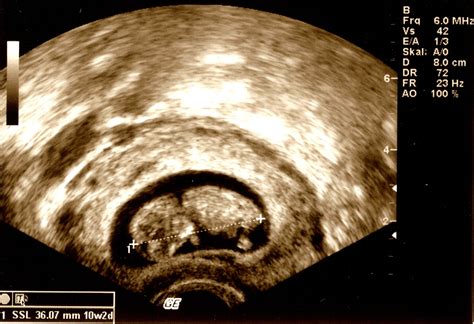

10 Week Fetus Ultrasound

A 10 week fetus ultrasound is a medical imaging technique used to visualize the fetus inside the uterus. At this stage, the fetus is about the size of a small strawberry, measuring approximately 3.1 cm (1.2 inches) in length from crown to rump. The ultrasound provides valuable information about the fetus's development, including the heartbeat, size, and overall health.

• Fetal Measurements: The ultrasound technician will measure the fetus's crown-rump length (CRL) to assess growth and development.

• Yolk Sac: This structure, which provides early nutrition to the embryo, is visible and helps confirm the viability of the pregnancy.

• Amniotic Sac: The amniotic sac, which contains the amniotic fluid surrounding the fetus, is also visible.

• Placenta: The placenta, which provides oxygen and nutrients to the fetus, begins to form and can be seen on the ultrasound.